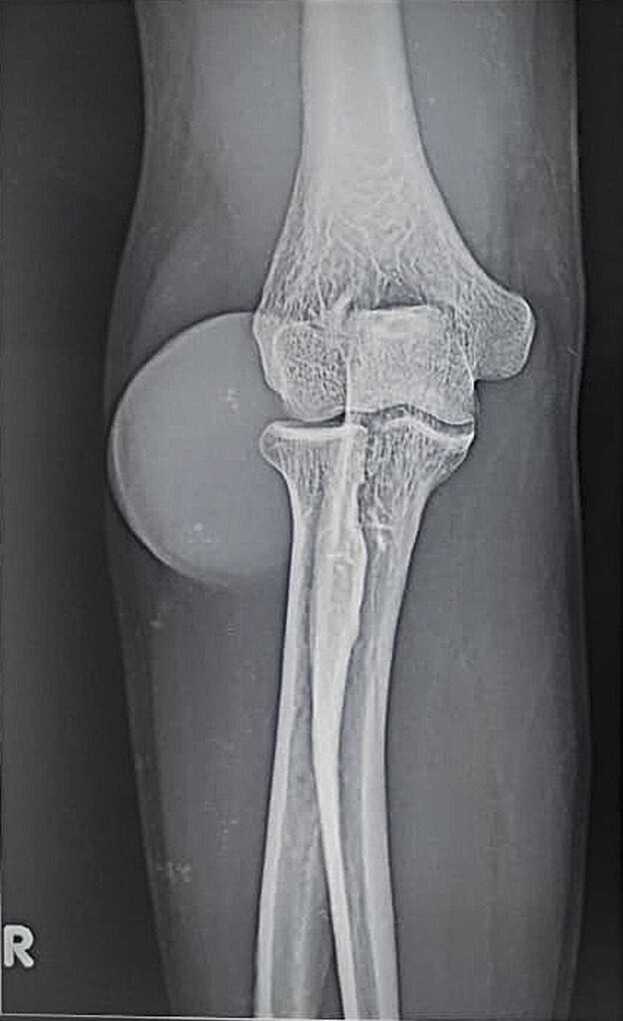

褐丝菌性囊肿是一种常见的皮下形式的褐丝菌病,患者可表现为皮下斑块、结节等,这是一种罕见的表现,在免疫功能低下的个体中报道最多。诊断是由组织病理学和真菌学证明的生物体。治疗是手术切除和全身抗真菌药物。我们报告一例罕见的无症状真菌囊肿在免疫正常的个体。

Phaeohyphomycotic cyst is a common subcutaneous form of phaeohyphomycosis in which patients can present with subcutaneous plaques, nodules, etc., It is an infrequent presentation and is most reported in immunocompromised individuals. Diagnosis is confirmed by histopathological and mycological demonstration of the organism. The treatment is by surgical excision with systemic antifungals. We report a rare case of asymptomatic Mycotic cyst in an immunocompetent individual.